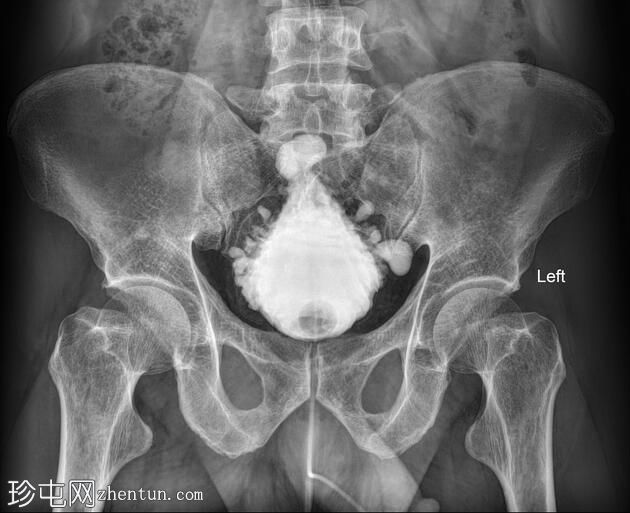

圣诞树膀胱

尿流细弱。有脊柱外伤史。

年龄:50岁

性别:男

逆行膀胱造影

透视检查

通过留置导尿管注入造影剂后,可见膀胱呈细长状,边缘不规则且呈小梁状,并可见多个小憩室,形似圣诞树。

病例讨论

本病例展示了一例尿流细弱且有脊柱外伤史的患者,其膀胱呈圣诞树状,符合

神经

源性膀胱的

影像

学表现。